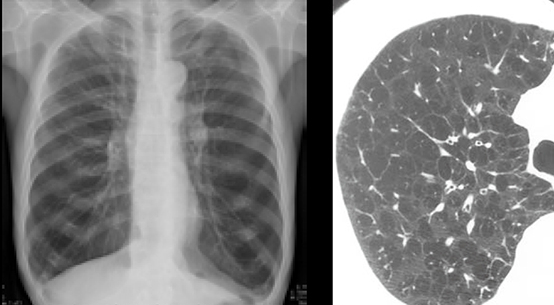

(1) 폐렴

폐렴은 폐조직에 염증이 발생하는 감염성 질환으로, 바이러스, 박테리아, 곰팡이 등 여러 원인에 의해서 발생할 수 있습니다. 주요 증상으로는 기침, 발열, 호흡 곤란 등이 있습니다.